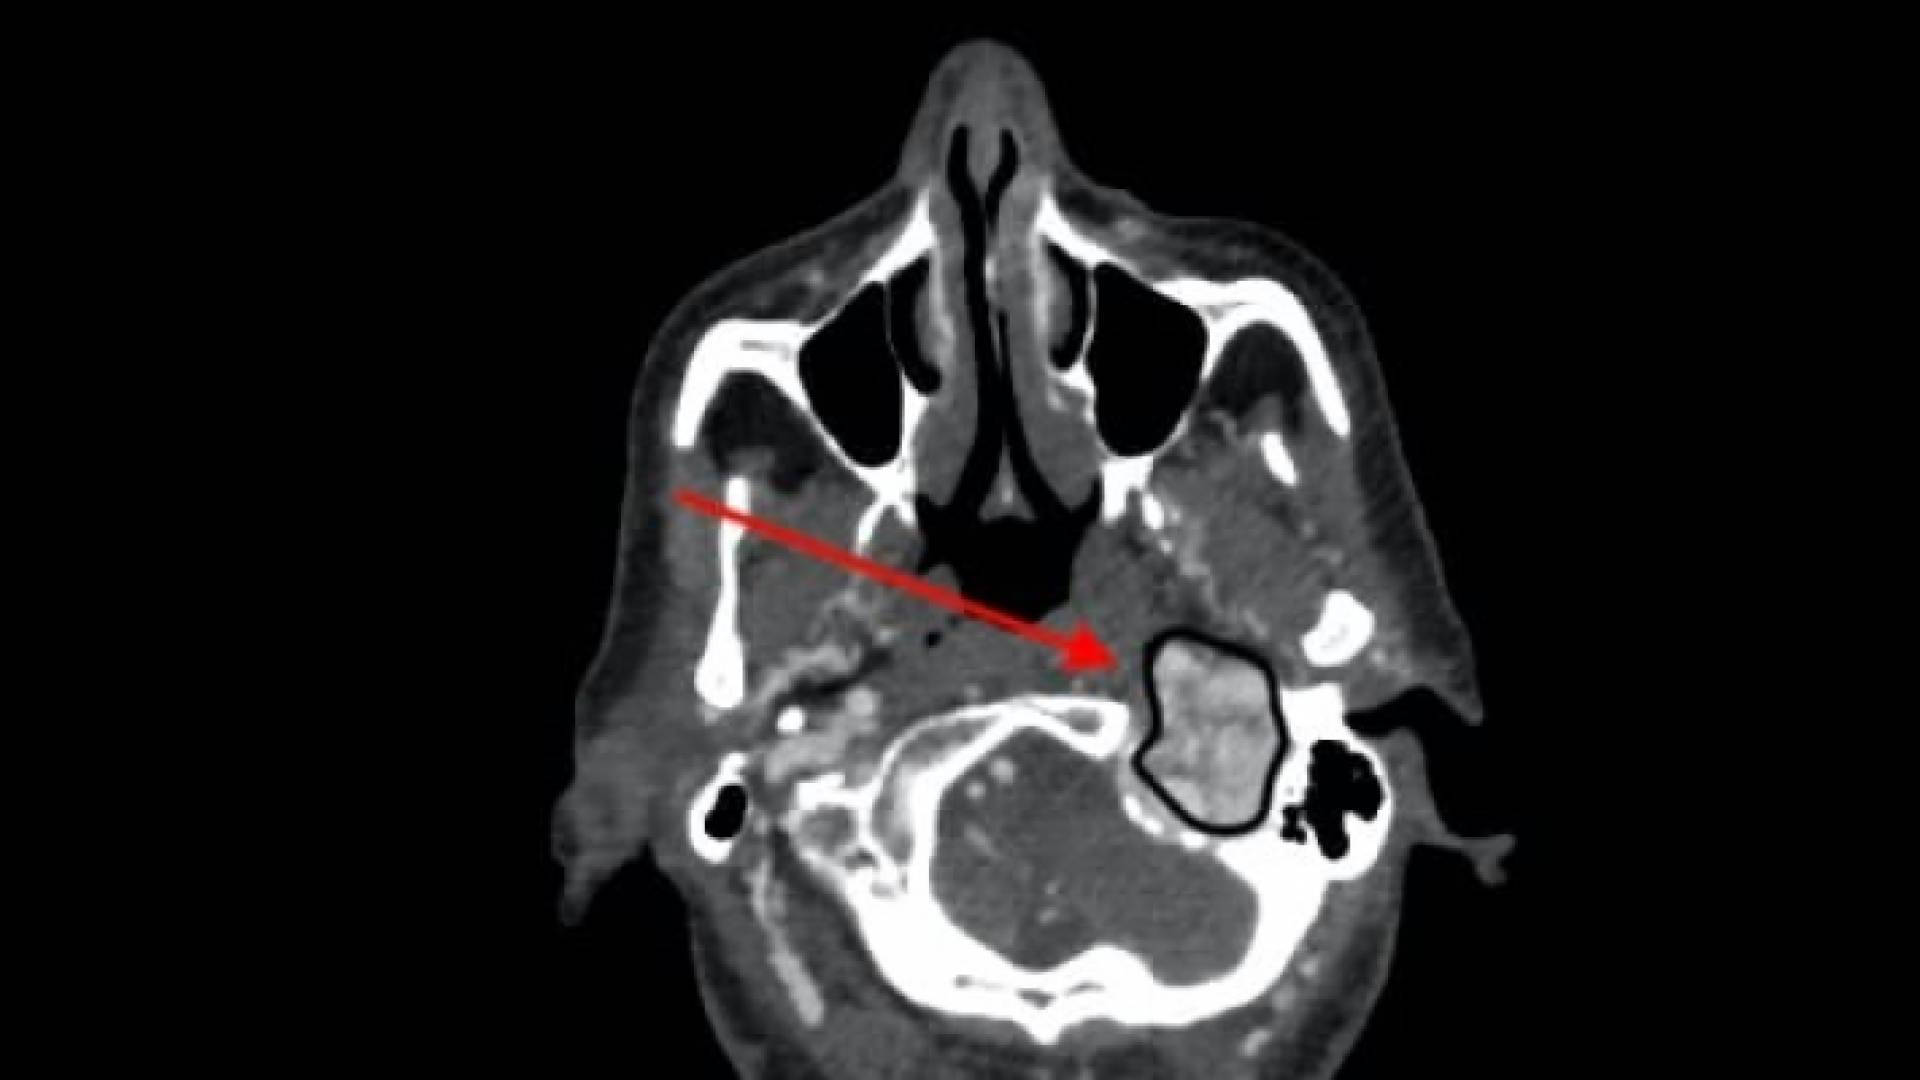

تمكن فريق مشترك من اطباء الاذنية واطباء جراحة الدماغ والاعصاب واطباء الاوعية الدموية والشرايين، من اجراء عملية نادرة ومعقدة تمثلت باستئصال ورم وداجي دماغي لمريضة تبلغ من العمر 50 عاما.

وبين اعضاء الفريق الطبي ان المريضة تعاني من خمسة اورام مستقتمات متزامنة، في الرقبة وقاع الجمجمة والصدر الامر الذي يعتبر نادر الحدوث عالميا. واوضح العقيد الطبيب امجد العسعس مستشار الانف والاذن والحنجرة وقاع الجمجمة ان هذه الحالة لاستئصال الاورام الدماغية الوداجية والأورام الكبية الطبلية تعد الحالة الخامسة التي تجرى من قبل فريق جراحة اورام قاع الجمجمة في مدينة الحسين الطبية.